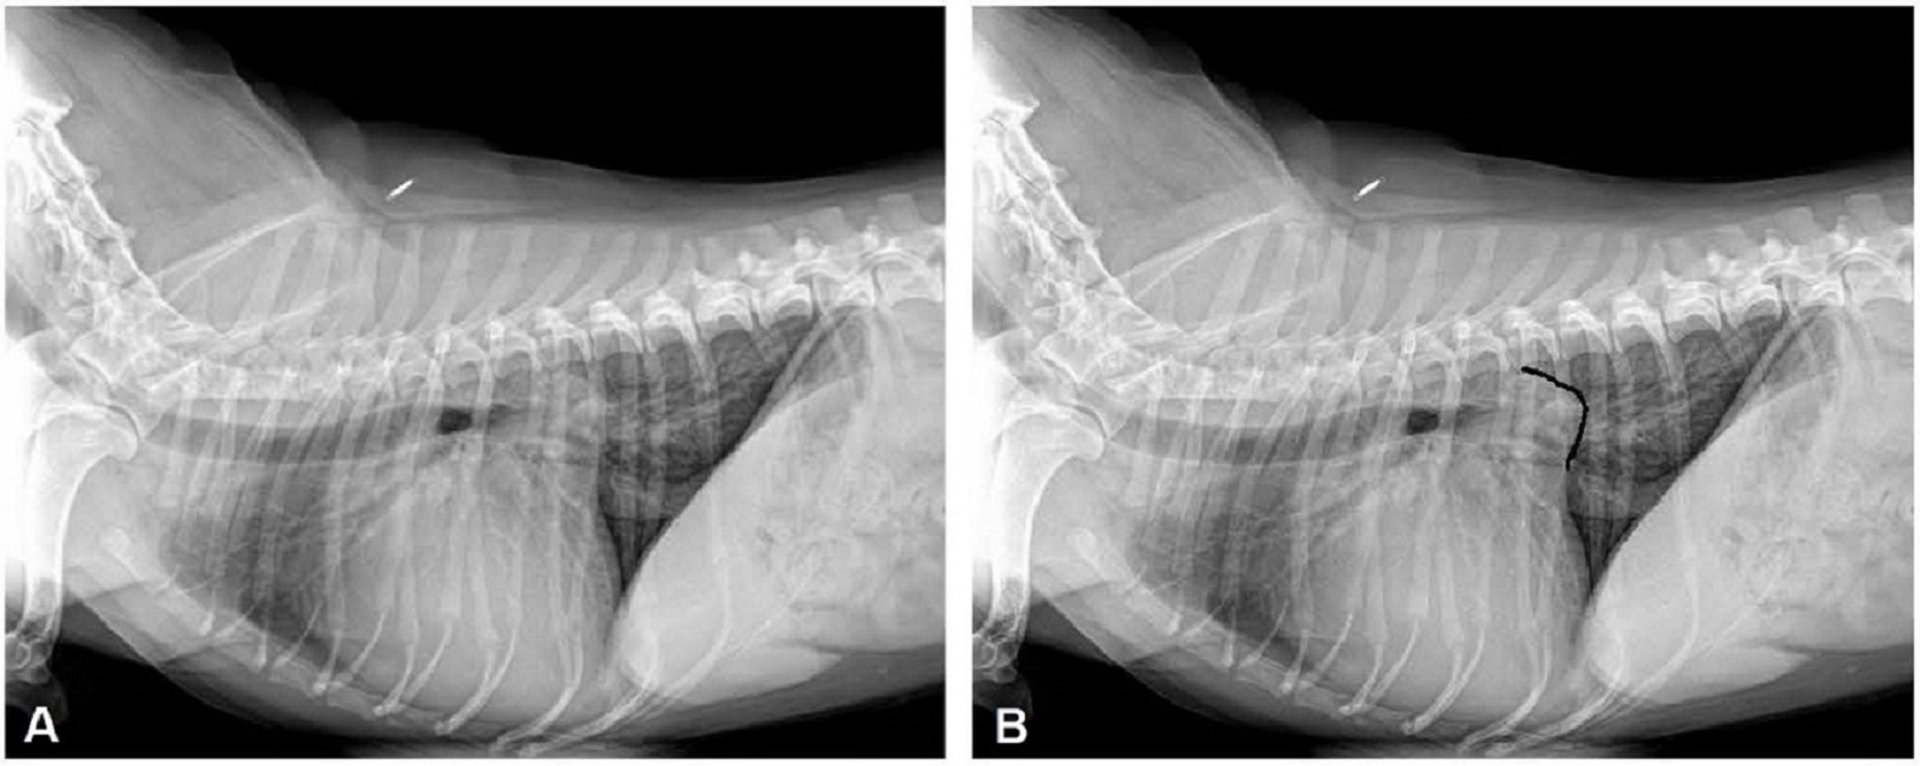

Figure 1 - Lateral thoracic radiograph of a dog with left-sided CHF showing cardiomegaly with left atrial enlargement, dorsal elevation of the trachea, and perihilar pulmonary edema pattern. (A). cardiogenic pulmonary edema due to severe mitral regurgitation and (B) body of the left atrium almost touching the spine. Courtesy of Dr. Mark D. Kittleson. Accessed from https://www.merckvetmanual.com/multimedia/image/congestive-heart-failure-dog-radiograph

- Radiography: Left atrial enlargement (dorsal deviation of trachea, splaying of mainstem bronchi), left ventricular enlargement, pulmonary venous distension

Radiographic Signs of Left-Sided CHF

- Cardiomegaly: Increased VHS, loss of waist, increased sternal contact

- Left atrial enlargement: Dorsal elevation of trachea and carina, splaying of mainstem bronchi

- Pulmonary venous distension: Veins larger than accompanying arteries

- Pulmonary edema: Perihilar to caudodorsal distribution, interstitial to alveolar pattern

- Figure 1: Lateral thoracic radiograph - Congestive heart failure with pulmonary edema. Source: Merck Veterinary Manual - Multimedia. Available at: https://www.merckvetmanual.com/multimedia/image/congestive-heart-failure-dog-radiograph (Free educational use)